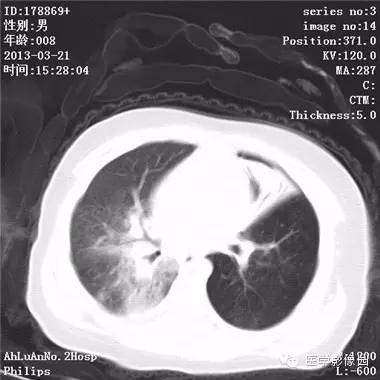

患儿男,8个月,呛咳,发热一周。实验室检查白细胞及中性粒细胞增高。

两肺肺纹理增多、增粗,右肺可见斑片状、片絮状模糊影,边界欠清;左肺上叶见楔形高密度影,内可见支气管征,尖端指向肺门;左肺下叶肺野透亮度增强;另见左肺主支气管内可见块状软组织密度影。

支气管异物(花生米)伴两肺炎症(追问病史,患儿奶奶层于一周前喂食患儿花生米,当时疑似“呛进去”,后来见好了也就没留意)。